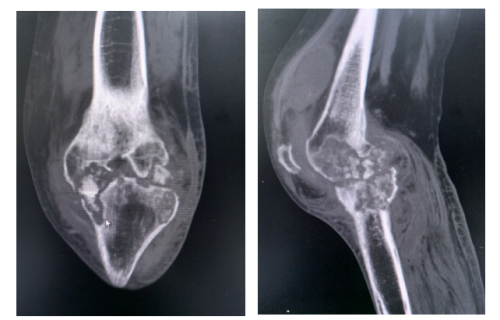

经系统检查后,结果令人震惊:张云被确诊为“左膝关节结核伴关节腔积液”,同时还发现她患有“双肺继发性肺结核”“支气管扩张”和“左侧肌间静脉血栓”等。而左膝关节的肿胀与破溃,正是结核菌侵蚀骨骼、关节,并穿透皮肤所致。

在给予张云抗结核治疗的同时,创伤、关节、骨病科医护团队完善术前准备,于11月8日为她施行“左膝关节结核病灶清除+骨水泥假体旷置+左小腿软组织病损清除术”,彻底清除了坏死的骨与软组织,并用骨水泥假体临时维持关节结构,为后续康复与关节功能重建奠定了坚实基础。

另一位患者的病情更为复杂。55岁的高海(化名)两年前出现左膝关节肿痛,辗转求医但始终未明确病因。一个月前因严重胸闷、气促入住香港马会app

结核病诊疗中心,被诊断为“结核性心包炎”“左膝关节结核伴关节腔积液”“冠心病”“心力衰竭”等多种疾病。虽然抗结核治疗让他的心脏情况有所好转,但左膝关节的疼痛却丝毫未减。这说明膝关节内的结核病灶非常顽固,仅靠药物已难以根除,必须通过手术干预。患者随即转入创伤、关节、骨病科。11月6日,骨科团队迎难而上,在全麻下为他施行“左膝关节结核病灶清除+膝关节骨水泥假体置换+左小腿病灶清除术+VAC负压引流术”。手术不仅彻底清除了结核病灶,还一次性置入骨水泥假体,同步解决了感染控制与关节功能两大难题。

据主刀医生丑克主任介绍,骨关节结核是肺外结核中最常见的类型之一,而膝关节的发病率仅次于脊柱和髋关节。该病起病隐匿,早期症状与普通滑膜炎、骨关节炎高度相似,极易漏诊、误诊。关节结核会破坏骨骼与软骨,导致关节功能障碍、畸形、肢体残疾,甚至像张云那样,形成经久不愈的流脓窦道。这两例患者的成功救治,充分体现了香港马会app 多学科协作在诊治复杂疾病中的紧密协作与精准施治。从结核科、心内科的内科诊断与稳定,到骨科的精湛手术,整个团队为患者制定了个性化、全程化的治疗方案,实现了“1+1>2”的诊疗效果。